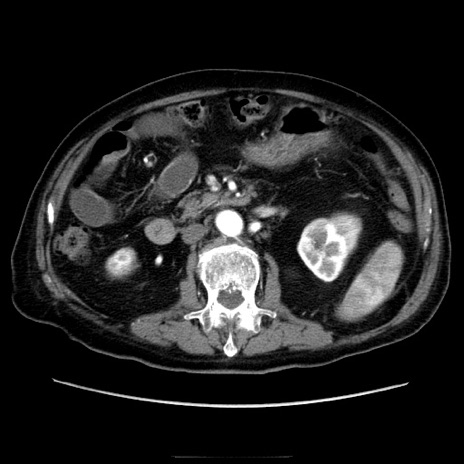

症例21(横断像)

【症例】70歳代男性

【主訴】腹痛

【現病歴】肝硬変・肝細胞癌にてかかりつけの方。約9時間前に食後より腹痛出現。症状が徐々に増悪し、嘔吐出現したため来院。

【既往歴】肝硬変、肝細胞癌(RFA、TACE後)

【身体所見】意識清明、表情苦悶様、BT 36℃、BP 129/78mmHg、P 88bpm、SpO2 97%(RA)、右上腹部から心窩部にかけて圧痛あり、反跳痛なし、筋性防御あり。

【データ】WBC 5800、CRP 0.16